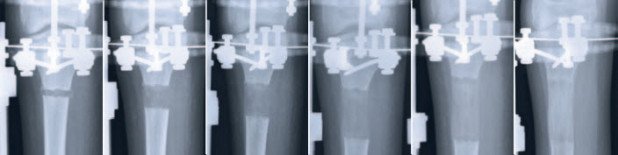

Fünf bis zehn Tage nach der Operation beginnt man mit der eigentlichen Verlängerung des Knochens. Das bedeutet, dass die Stelle, wo der Knochen durchtrennt wurde, einen Millimeter pro Tag auseinander gezogen wird. In diesem Prozess wächst zwischen den beiden Knochenenden ein so genannter Distraktionscallus, der aus einer noch nicht verkalkten und daher weichen Knochengrundsubstanz besteht. Der Callus lässt sich nun auf die gewünschte Länge dehnen. Wenn nötig, kann dabei gleichzeitig auch eine Achsenkorrektur des Knochens vorgenommen werden. Da der Knochen strikt um einen Millimeter pro Tag verlängert wird, kann der neu gebildete Knochen optimal nachreifen. Eine Verlängerung von 5 Zentimetern benötigt somit eine Verlängerungszeit (Distraktionsphase) von etwa 50 Tagen.

Nach der Distraktion muss der neue Knochen (Distraktionscallus) wieder die Struktur des ursprünglichen Knochens annehmen. Im Normalfall sieht man in den Röntgenbildern eine zunehmende Kalkdichte der Verlängerungsstrecke. Ist diese annähernd so dicht verkalkt wie der umgebende normale Knochen (siehe Deckblatt), kann der Apparat entfernt werden.